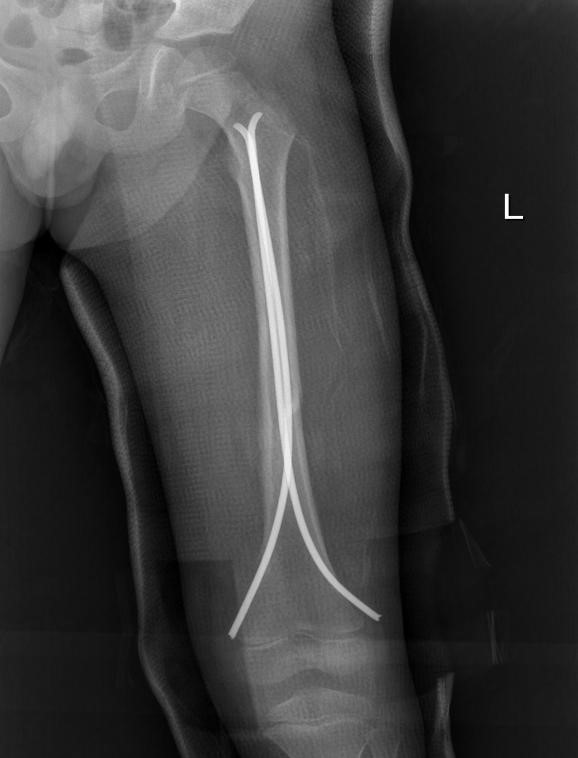

患者术后影像资料